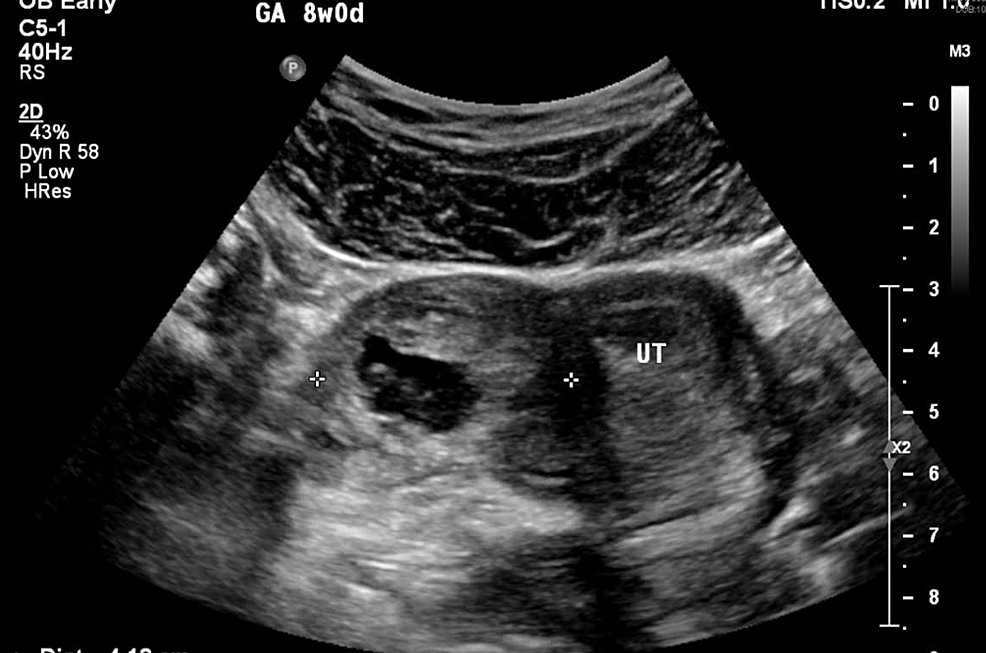

عکس سونوگرافی بارداری خارج از رحم